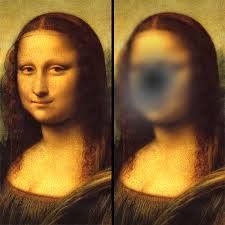

El propósito de este trabajo fue estudiar el rendimiento de lectura de los pacientes con enfermedad de Stargardt, y la relación entre las mediciones clínicas de la visión y la calidad de vida relacionada con la visión.

Se estudiaron ambos ojos de 16 pacientes con enfermedad de Stargardt. A cada paciente se le examinó la agudeza visual corregida (ETDRS), la capacidad de lectura (tablas MNREAD y REX),la sensibilidad al contraste (test Pelli-Robson), el estudio de fijación (microperímetro MP1), y la relación visión-calidad de vida ( test NEI VFQ-25). El patrón de correlación entre estas variables se examinó y se utilizó un análisis factorial exploratorio para investigar dimensionalidad tanto de la función visual y la calidad de vida relacionada con la visión.

La media de agudeza visual (ETDRS) fue de aproximadamente 20/160 (0,9 logMAR). Todas las medidas psicofísicas estudiadas fueron altamente o moderadamente correlacionadas con la velocidad de lectura MNREAD (p <0,05). Se encontró una correlación similar entre las medidas psicofísicas y las de calidad de vida, que fue superior para las medidas de agudeza (r = -0,75) y velocidad (r = 0,74) en la lectura. En consecuencia, el análisis factorial exploratorio sugiere que una sola dimensión latente explica la mayor parte de la varianza de medidas psicofísicas de visión, así como de la calidad de vida relacionada con la visión.

En conclusión, la capacidad de lectura debe ser evaluada en pacientes con enfermedad de Stargardt, ya que encontramos que tanto la velocidad de lectura y la agudeza visual son fuertes determinantes de la calidad de vida.